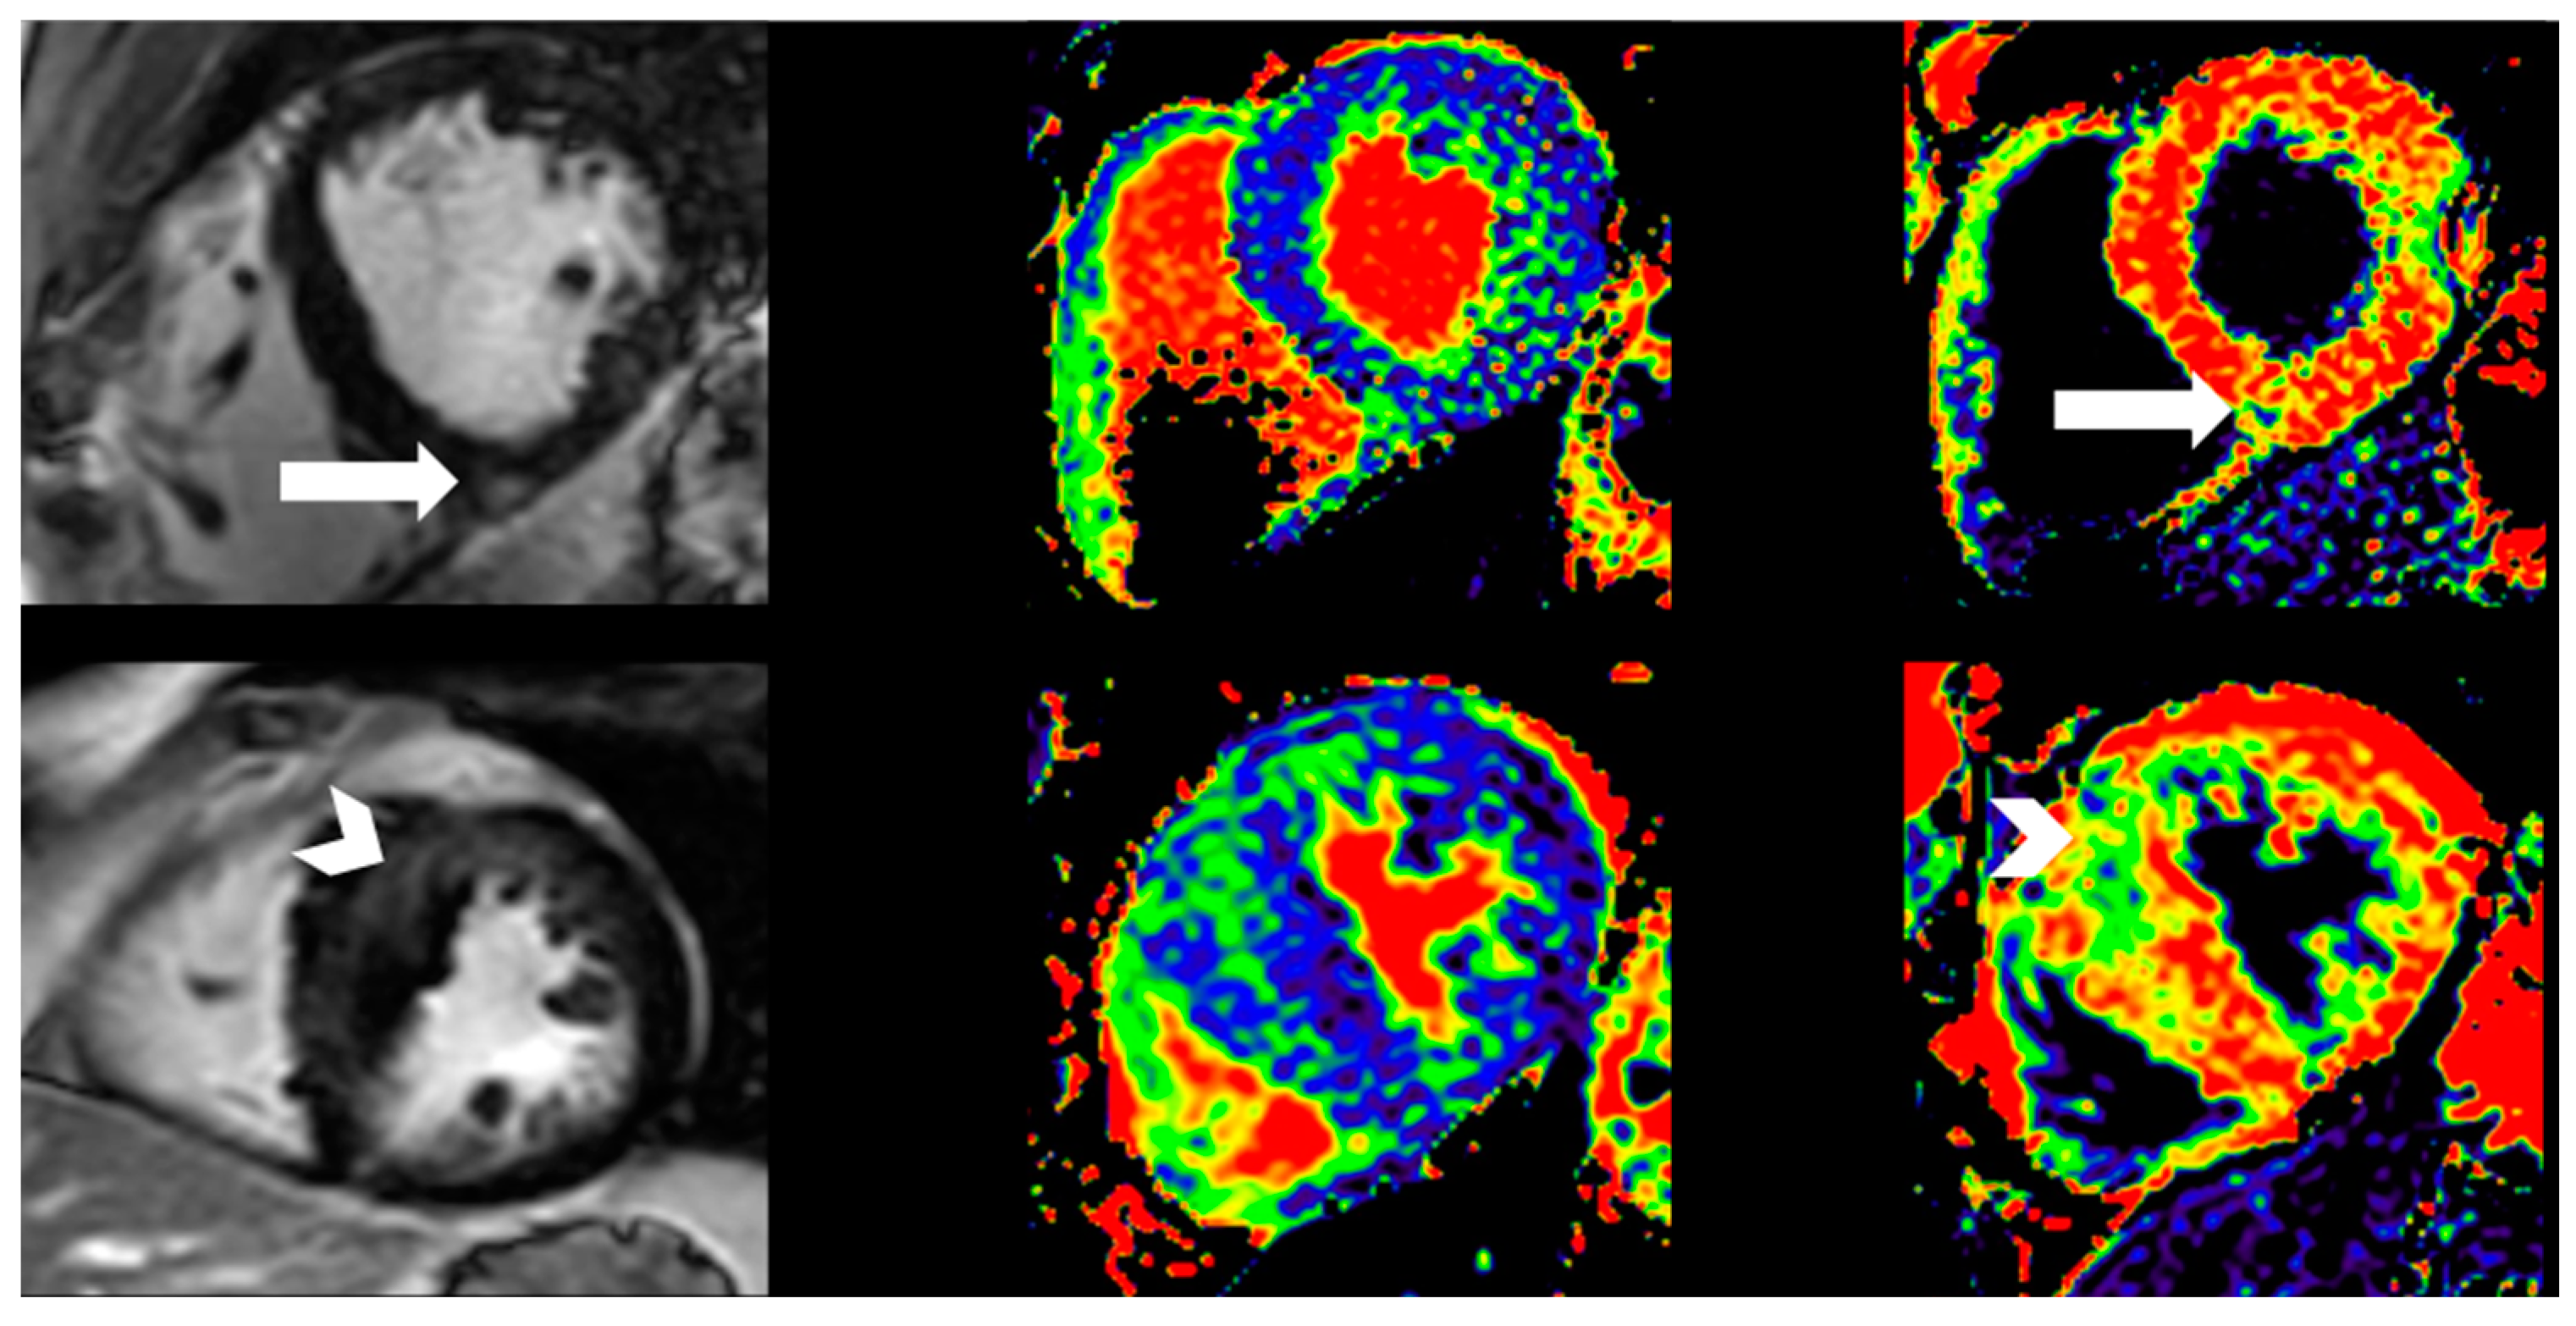

| Extracellular volume, % | 22.7 ± 3.2 | 25.6 ± 4.1 | 0.013 |

| Late gadolinium enhancement, n (%) | 1 (3) | 8 (40) | 0.001 |

| Native T1 time, ms | 1204 (1191, 1234) | 1265 (1255, 1312) | <0.001 |

| Extracellular volume, % | 22.7 ± 3.2 | 25.6 ± 4.1 | 0.013 | >22.5 | 0.75 | 0.60–0.89 |

| Native T1 time, ms | 1204 (1191, 1234) | 1265 (1255, 1312) | <0.001 | >1230 | 0.83 | 0.71–0.96 |